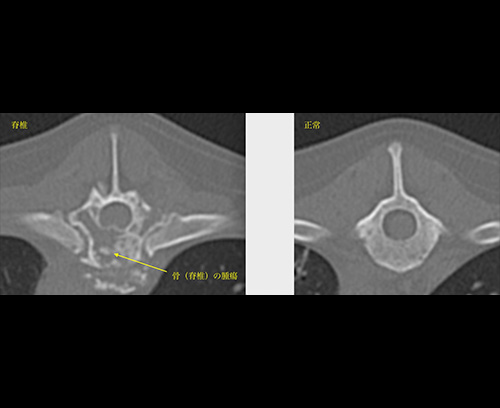

骨肉腫(骨の悪性腫瘍)